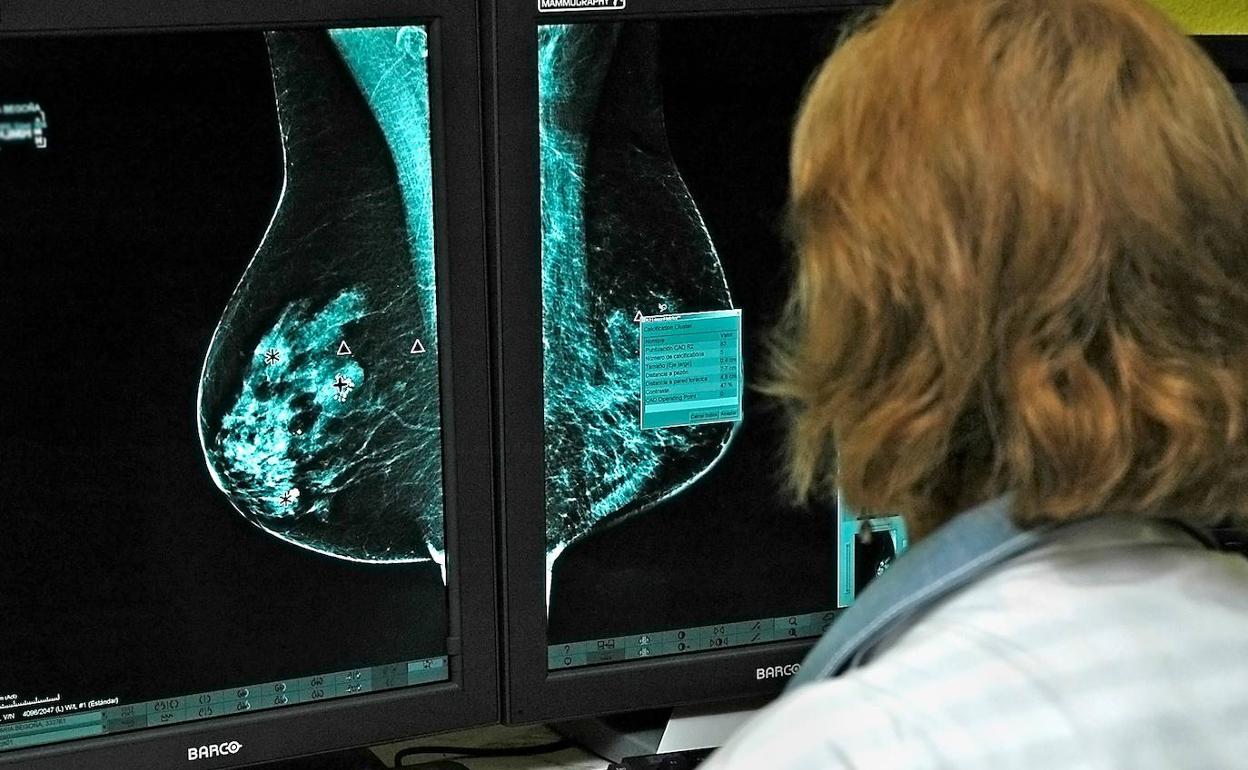

Investigadores del Laboratorio de Oncología Matemática de la Universidad de Castilla-La Mancha (UCLM) han conseguido identificar un nuevo biomarcador de imagen para pronosticar la evolución de los cánceres de mama y de pulmón a partir del desarrollo de modelos matemáticos.

El estudio ha analizado los datos de 230 pacientes oncológicos de pulmón y mama de los hospitales de Albacete y Ciudad Real con el objetivo de captar la heterogeneidad de las células tumorales. Según el profesor del Departamento de Matemáticas de la UCLM e investigador de este laboratorio, Gabriel Fernández Calvo, «a partir de imágenes médicas, los investigadores han estudiado los niveles de actividad metabólica en pacientes con tumores de pulmón y mama, o lo que es lo mismo, cómo se va reorganizando dicha actividad conforme esos tumores evolucionan».